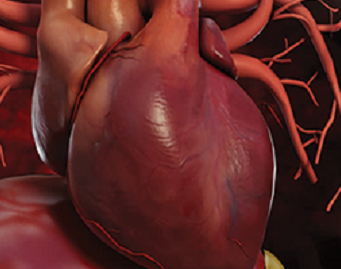

Bypass Surgery (CABG)

Dr. Ebrahim Patel provides specialised and comprehensive care to individuals who may want to undergo heart surgery. His knowledge in Coronary Artery Bypass Grafting (CABG).